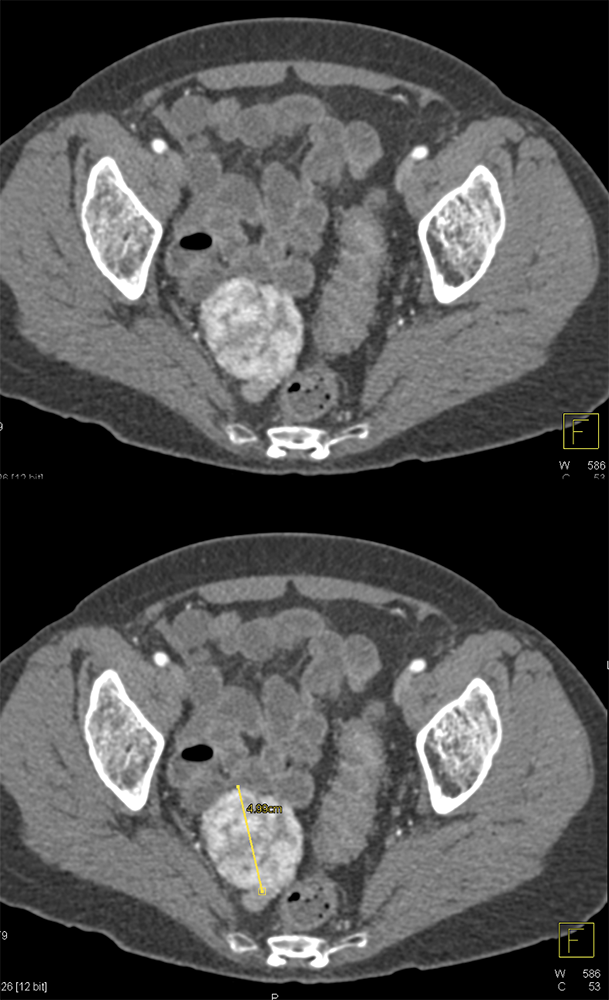

GI Bleed ![]() |

![]() |

“All patterns of enhancement on contrast enhanced computed tomography (CECT) can be seen with GISTs, including hypoenhancing, isoenhancing, and hyperenhancing tumors. They can be large or small, endoluminal or exophytic. Clinical presentations include asymptomatic patients, nonspecific symptoms, obstruction, and bleeding. Bleeding can take the form of slow, intraluminal GI bleeding or massive intraperitoneal bleeding secondary to rupture and can be seen regardless of the enhancement pattern.” Getting the GIST: a pictorial review of the various patterns of presentation of gastrointestinal stromal tumors on imaging. Scola D et al. Abdom Radiol 2017 May;42(5):1350-1364. |

“Occasionally, patients may present with GI bleeding, which may be occult or take the form of frank hemorrhage with hemodynamic instability. Likewise, tumors can rupture on the external surface, causing intraperitoneal hemorrhage which can be life threatening.” Getting the GIST: a pictorial review of the various patterns of presentation of gastrointestinal stromal tumors on imaging. Scola D et al. Abdom Radiol 2017 My;42(5):1350-1364. |